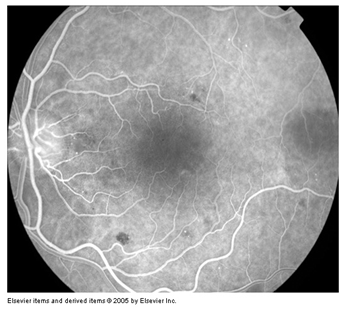

Is mainly divided into 1) blocked fluorescence and 2) vascular filling defect. Blocked fluorescence: Blocked fluorescence when stimulation or visualization fluorescein blocked by Blood. (Figure 12) (Figure 13) Pigment (Figure 14) Fibrosis vascular filling defect: (Figure 15) Vascular filling defect: Occurs when the retinal or choroidal vessels do not fill properly as in non-perfusion of artery vein. Capillary hyper fluorescence is mainly divided into 1) Autofluorescence 2) Transmission defect (window defect) 3) Leaking 4) Pooling and 5) Staining. Auto fluorescence: (Figure 16) compounds absorb blue light and emit yellow-green light in a similar fashion to fluorescein. It is imaged much more effectively by scanning laser ophthalmoscopy but can also be detected on standard fundus photography in exposed optic nerve head drusen and sometimes with Lipofuscin in retinal drusen and other abnormalities such as astrocytic hamartoma and angioid streaks. Transmission defect (window defect): (Figure 17) A window defect refers to the choroidal fluorescence produced by a relative decrease or absence of pigment in the RPE or an absence of RPE. The hyper fluorescence occurs early and reaches its greatest intensity with the peak of choroidal filling leaking: (Figure 18) Leakage of fluorescein dye is defined as hyper fluorescence of fluorescein in the extra vascular space. Typically the area of fluorescence increases in both size and intensity as the study progresses.

The borders of hyper fluorescence become increasingly blurred, & the greatest intensity of the hyper fluorescence is appreciated in the late phases of the study pooling: (Figure 19) (Figure 20) Pooling refers to the accumulation of fluorescein dye into an anatomical space. Pooling is seen in both neural retina and RPE detachments the margins of the space trapping the fluorescein are usually distinct. Staining: (Figure 21) Staining results from fluorescein entry into a solid tissue such as a scar, optic nerve tissue, or sclera the pattern of hyper fluorescence with gradually increasing intensity of fluorescence, but the borders of the hyper fluorescence remain fixed throughout the angiogram process.